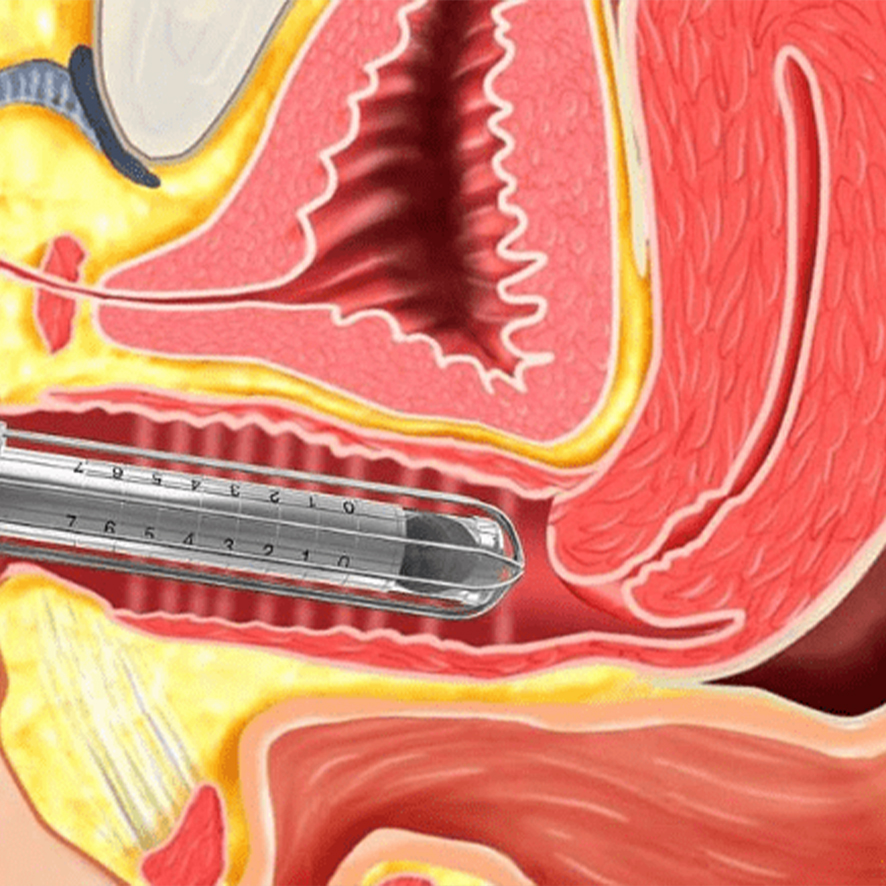

G30 yaş sonrası başlayabilen ve sıklığı yaş ile artan idrar kaçırma; koku, hijyen gibi sebepler nedeniyle kadınların kendini sosyal yaşamdan kısıtlamasına yol açan önemli bir sorundur. İdrar kaçırma sorunu genetik olarak doğuştan pelvik taban kaslarının zayıflığı nedeniyle de yaşanabilmektedir. Çok doğum yapma, sigara kullanımı, obezite, sağlıksız beslenme gibi risk faktörleri bulunmaktadır ve bu risk faktörlerinin varlığında daha erken yaşlarda görülmektedir.

Tedavi için başvuran hastalarda öncelikle detaylı bir hastalık öyküsü araştırılır. Doğum yapma sayısı, sigara kullanımı, kilo durumu, mevcut kronik hastalıkları, mesleği (ağır işlerde çalışıp çalışmadığı) sorgulanır. Çünkü karın içi basıncını artıran durumlarda idrar kaçırma daha sık görülebilir. Örneğin hastada öksürüğe yol açacak kronik bir solunum yolu hastalığı varsa öncelikle bu sorun tedavi edilerek idrar kaçırmaya sebep olan bu basınç ortadan kaldırılmalıdır. Bunun yanında cinsel hayatı aktif olmayan kadınlarda inkontinans daha fazla görülmektedir. Çünkü cinsel yaşam kadınlarda pelvik kaslarını geliştirdiğinden idrar kaçırmayı engellemektedir.